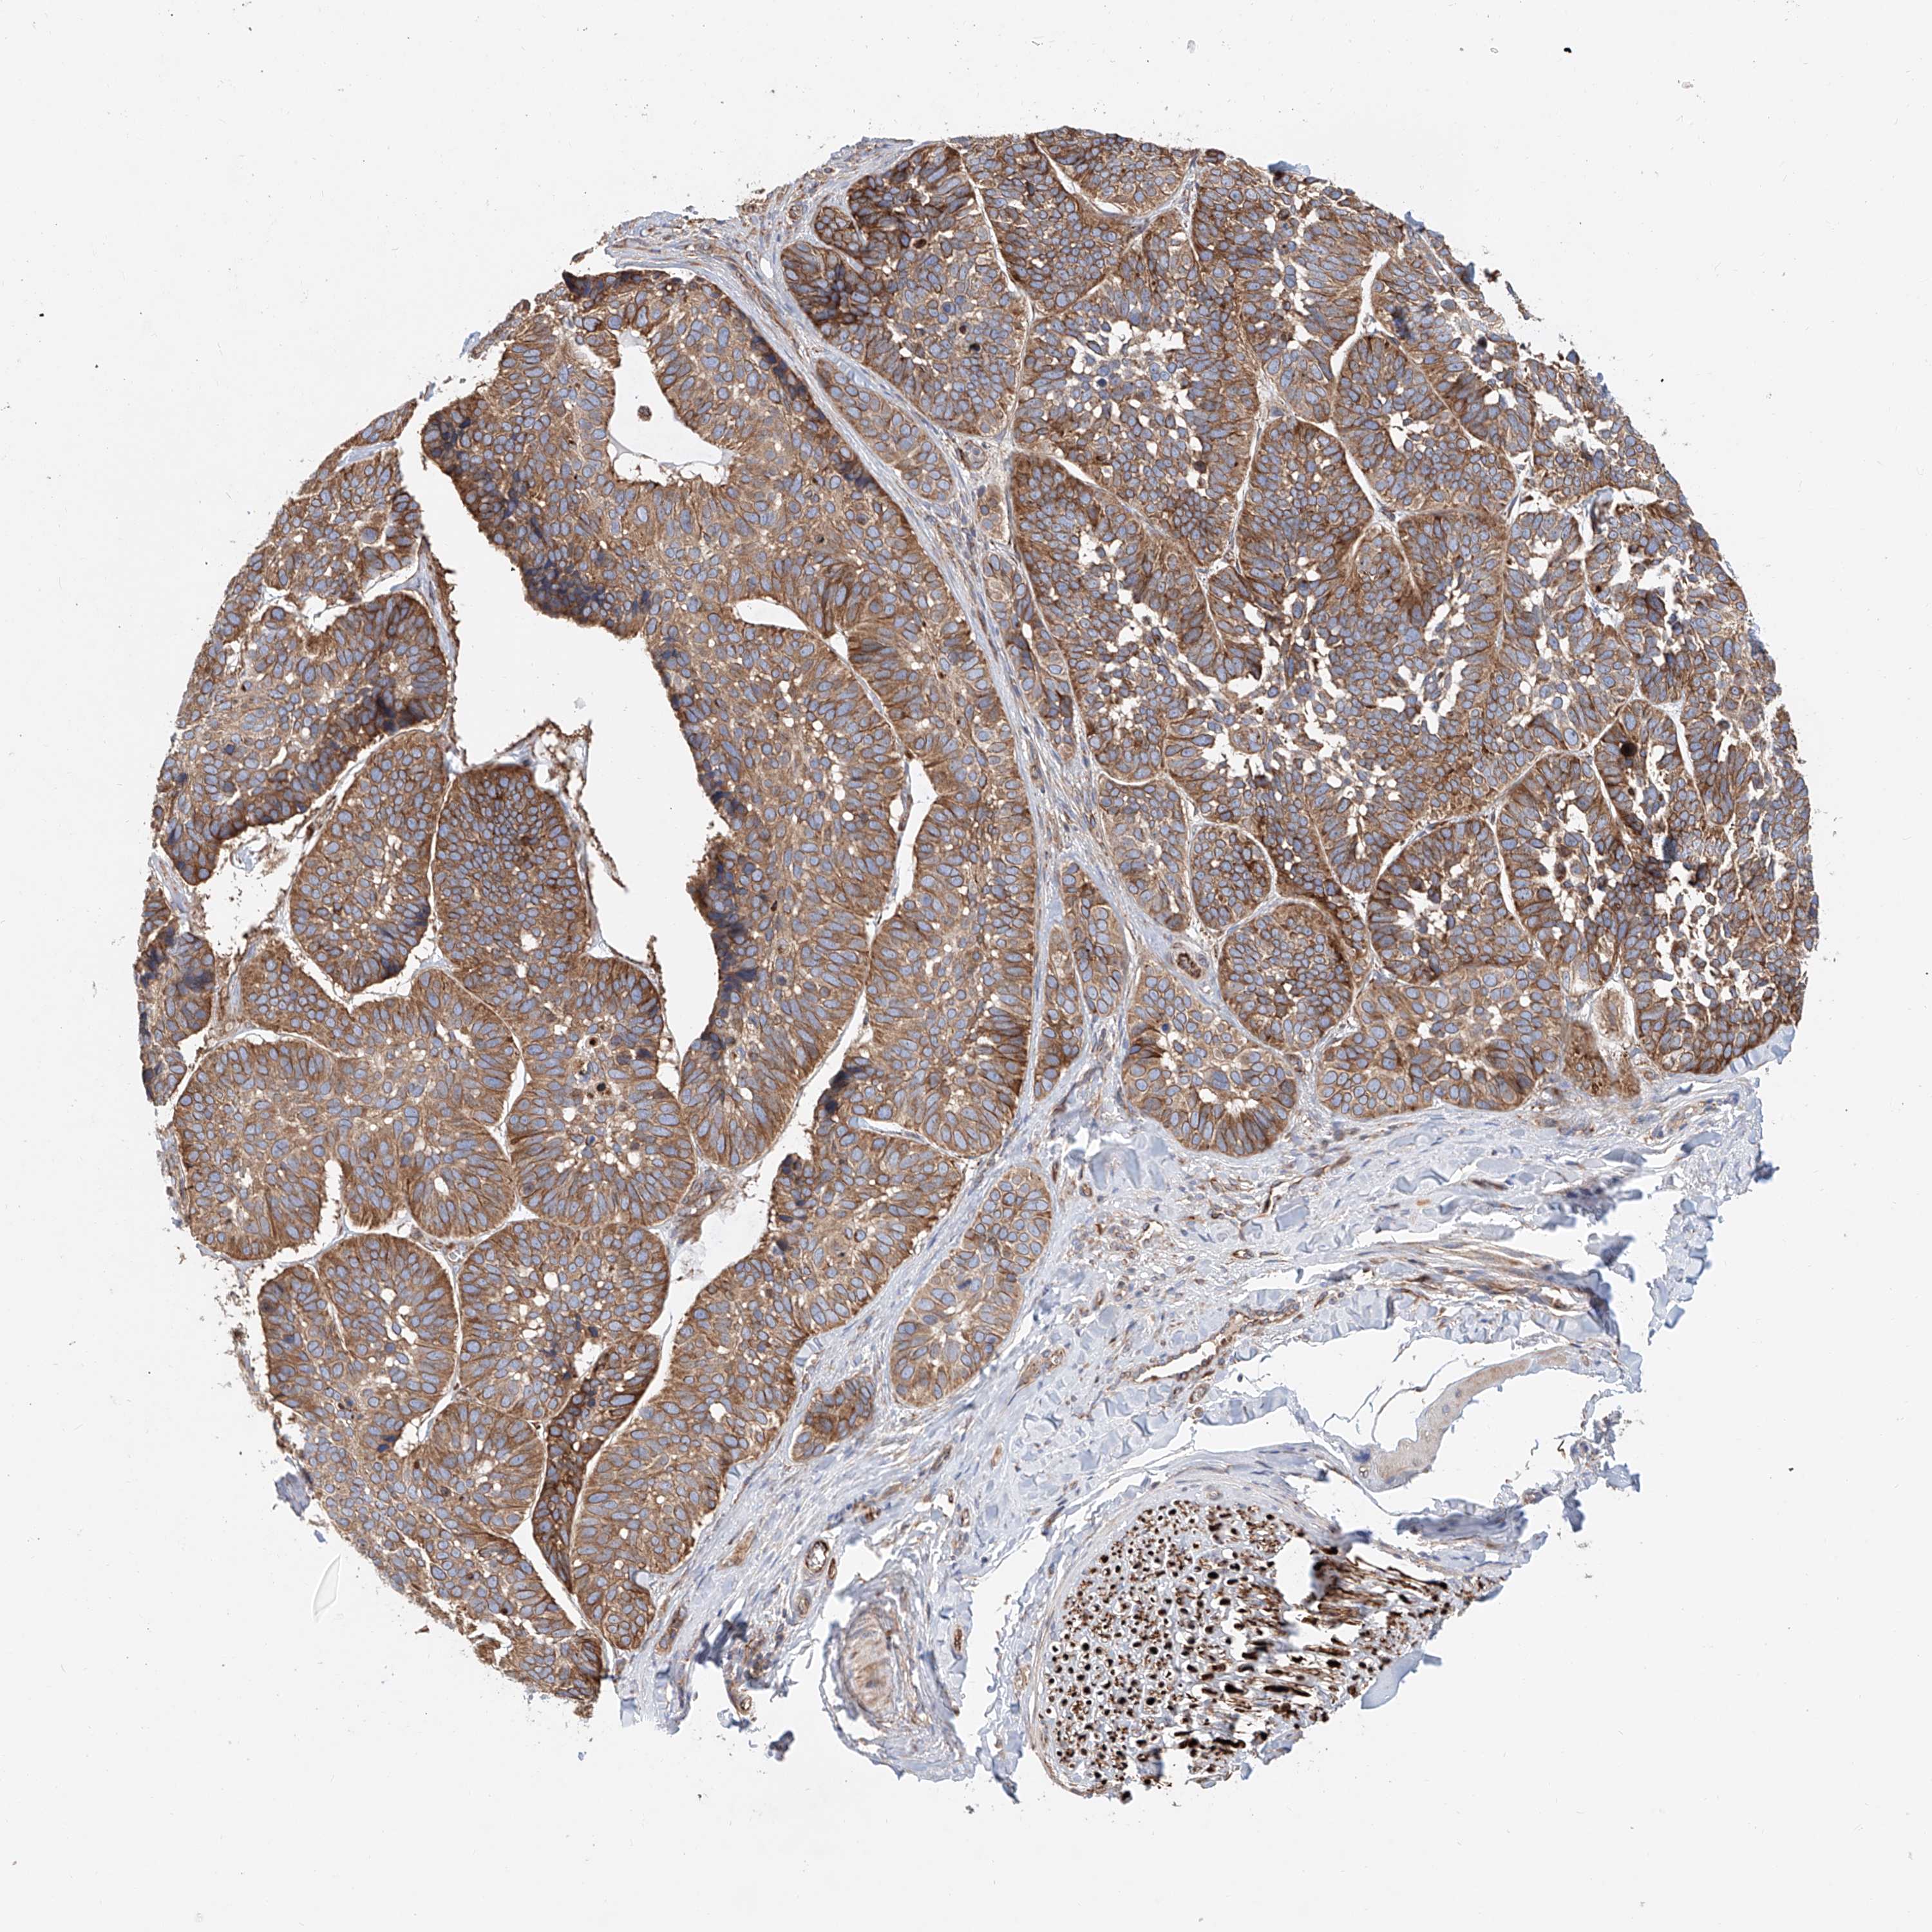

SKIN CANCER - Protein expressioni

A mouse-over function shows sample information and annotation data. Click on an image to view it in a full screen mode. Samples can be filtered based on level of antibody staining by selecting one or several of the following categories: high, medium, low and not detected. The assay and annotation is described here.

Antibody stainingi

Antibody staining in the annotated cell types in the current human tissue is reported as not detected, low, medium, or high, based on conventional immunohistochemistry profiling in selected tissues. This score is based on the combination of the staining intensity and fraction of stained cells.

Each image is clickable and will lead to virtual microscopy that enables deeper exploration of all samples and also displays staining intensity scores, fraction scores and subcellular localization as well as patient and tissue information for each sample.

Antibody HPA029578

Staining

High

Medium

Low

Not detected

Intensity

Strong

Moderate

Weak

Negative

Quantity

>75%

75%-25%

<25%

None

Location

Nuclear

Cytoplasmic/membranous

Cytoplasmic/membranous,nuclear

Basal cell carcinoma

Squamous cell carcinoma, NOS

Squamous cell carcinoma, metastatic, NOS